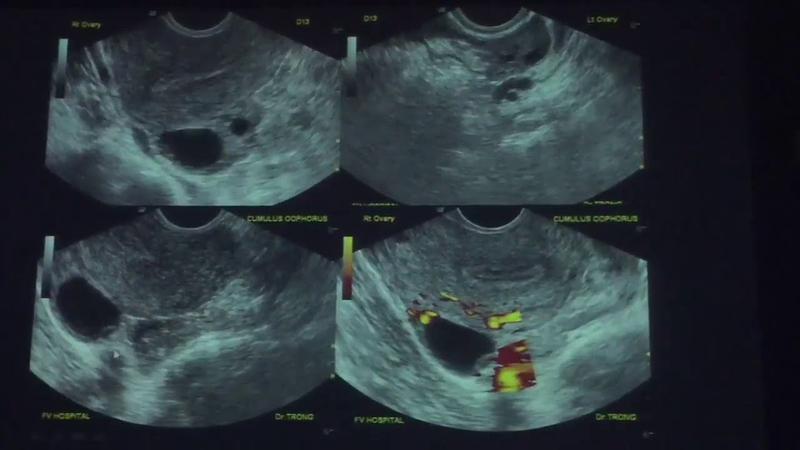

Nên đi siêu âm canh trứng vào thời điểm nào 3 Dựa vào hình ảnh siêu âm để xác định kích thước nang trứng, dự đoán thời điểm trứng rụng

Ví dụ, với một phụ nữ có chu kỳ kinh nguyệt 28 ngày thì nang trứng được mô phỏng như sau:

• Đầu chu kỳ, nang trứng rất nhỏ chỉ khoảng 4 - 5 mm, quan sát rõ qua siêu âm đầu dò âm đạo, qua siêu âm bụng khó nhìn thấy.

• Sang ngày thứ 7 - 8 của chu kỳ, kích thước lúc này của nó là 10 - 12 mm và tăng dần 1 - 2 mm kích thước qua từng ngày.

• Vào khoảng ngày thứ 14 của chu kỳ, nang trứng đạt mức 17 - 18 mm, kích thước đủ lớn và trưởng thành để rụng, xảy ra sự phóng noãn (hay còn gại là rụng trứng).

Như vậy, để bác sĩ có thể quan sát được kích thước nang trứng và đạt được mục đích soi trứng, bạn nên thực hiện quy trình này vào ngày thứ 10 của chu kỳ. Thực hiện liên tục theo tần suất 2 ngày một lần cho đến khi nang trứng đạt kích thước trung bình là 15 mm, sau đó thì thực hiện siêu âm ngày 1 lần cho đến khi trứng trưởng thành và rụng. Trứng rụng đạt chất lượng tốt nhất khi noãn nang đạt 20 - 28 mm.